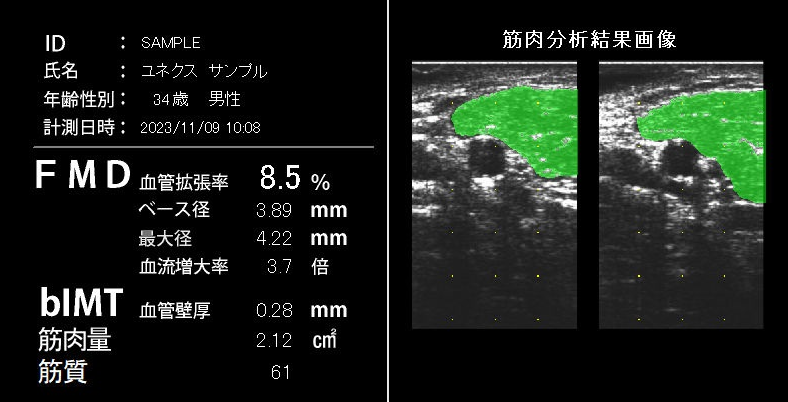

筋肉分析のご紹介

■ユネクスイーエフは FMDの値と共に、上腕二頭筋の筋肉量と筋質(霜降り度)が算出可能です。